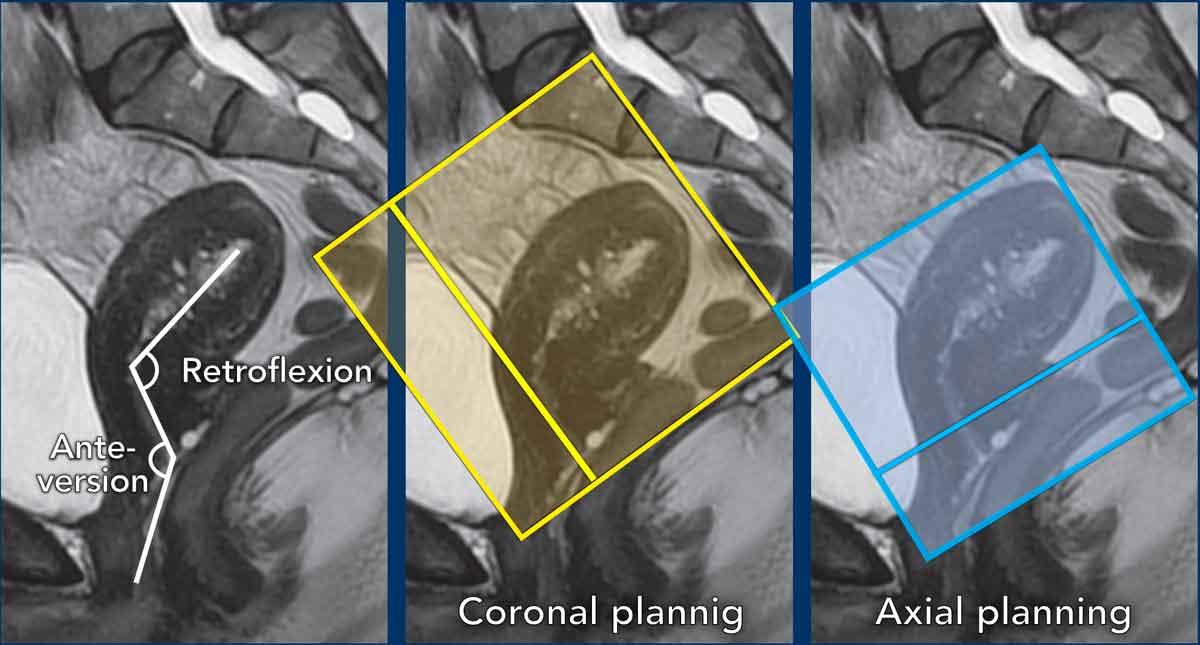

Lập kế hoạch chuỗi xung

Các chuỗi xung MRI được lập kế hoạch dựa theo trục dài của ống cổ tử cung.

Mặt phẳng axial vuông góc với trục dài của ống cổ tử cung.

Mặt phẳng coronal song song với trục dài của ống cổ tử cung.

Lưu ý: các biến thể giải phẫu cổ tử cung

Cần tính đến vị trí của ống cổ tử cung và lập kế hoạch các chuỗi xung MRI vuông góc và song song tương ứng.

Ví dụ minh họa cách góc gập và đặc biệt là hướng nghiêng ảnh hưởng đến việc lập kế hoạch chuỗi xung.

Trong trường hợp này, cổ tử cung ở tư thế nghiêng trước (anteversion) và thân tử cung ở tư thế gập sau (retroflexion).

Cần nhớ rằng trong ung thư cổ tử cung, các chuỗi xung axial được lập kế hoạch vuông góc với ống cổ tử cung.

Một ví dụ khác cho thấy cổ tử cung ở tư thế nghiêng sau (retroversion) và thân tử cung ở tư thế gập trước (anteflexion).

Quan sát cách biến thể tư thế này ảnh hưởng đến việc lập kế hoạch chuỗi xung tương ứng.